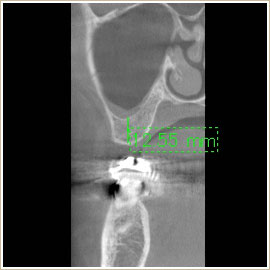

インプラント

CTはインプラント治療には欠かせない診査法です。

治療前の診断、治療中の確認、その後のメインテナンスにも必要です。

埋入するインプラントの埋入角度、深度、直径等を術前に綿密にシュミレーションします。

▼治療前

▼治療後